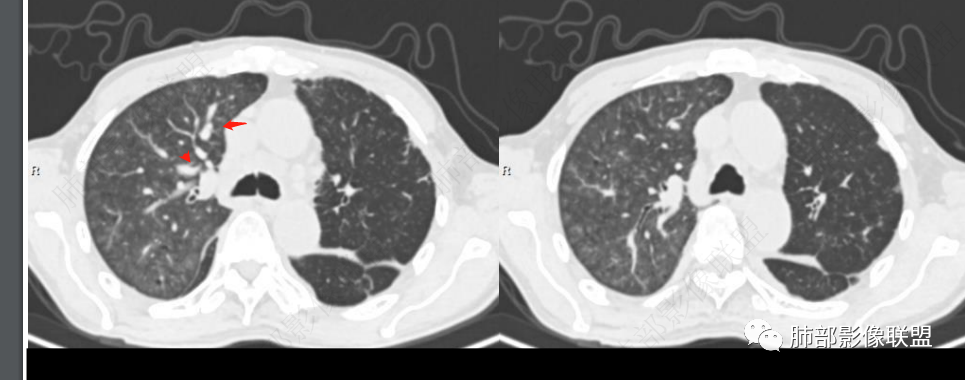

左丶右肺明显透过不均,左肺透过增强,血管明显纤细,部分马塞克征,无小气道闭塞史,故存在血管因素。→pE。

左右不对称累及,造成双肺改变的疾病可能小。

@曹冠杰,济医附院?一侧肺栓塞,右心血流到另一侧无栓塞的肺动脉,故而高灌注,可以肺水肿。少见模式,肺栓塞对侧肺水肿。

4.左肺相对广泛低密度、血管纤细(显著)。

(2)“马赛克”征:肺内灌注不均匀,表现为正常的肺组织代偿性高灌注与栓塞所致相应肺组织灌注下降相间存在。